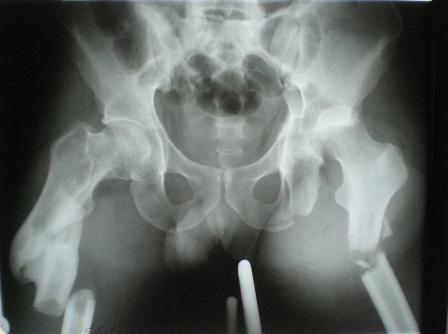

Пациент 33 лет поступил 1.02.08 с диагнозом: Множественная травма.

Т-образный перелом свода, перелом заднего края правой вертлужной

впадины. Поперечный подвертельный перелом диафиза, подвздошный вывих

правого бедра. Поперечный подвертельный перелом диафиза на фоне

консолидированного косого перелома в\3 левого бедра в порочном

положении. Открытый краевой перелом надколенника правого коленного

сустава. Открытый оскольчатый перелом н\челюсти. Закрытый неосложненный

перелом V ребра справа. В настоящее время больной компенсирован.

Планируем: в положении больного на спине выполнить БИОС левого бедра

ретроградно. После повернуть на левый бок и выполнить БИОС правого бедра

антеградно одновременно с Y-образным доступом к вертлужной впадине.

После - остеосинтез вертлужной впадины реконструктивными пластинами.